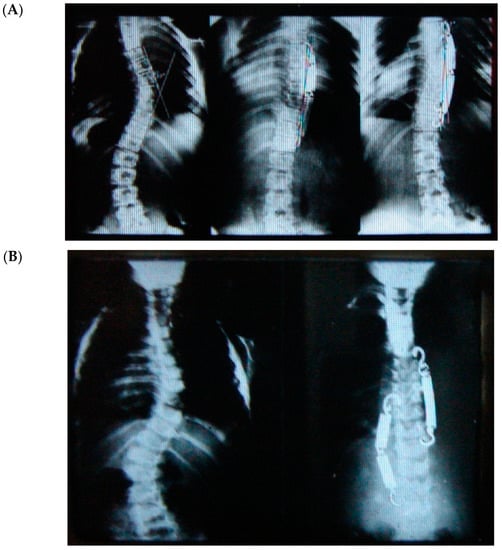

Correction of two (scoliosis and hypokyphosis) of the three plane deformities in scoliosis has already been explained, but how rotational correction happens in these growth-friendly procedures is not clear. We know that with the progression of scoliosis, the rotation of the vertebral bodies towards the concavity increases due to the imbalance/disturbance of the different growth plates and synchondrosis in the growing spine. Tethering, either anterior or posterior, on the convexity of the curvature locks this progressive abnormal rotation and may allow the opposite side to de-rotate the vertebrae gradually with growth, thereby improving the rotational deformity and the rib hump, as shown (Figure 2).

Figure 2.

Radiological regression of rib hump with decrease of the prominent ribs.

All three cases were thoracolumbar scoliosis (Lenke 5C) with an apex between T12 and L1 (Figure 3, Figure 4 and Figure 5).

Figure 3.

A 14-year-old adolescent. (A) Pre-op. (B) Immediate post-op. (C) One-year follow up.

Figure 4.

A 13-year-old adolescent. (A) Pre-op. (B) At 6-month follow up.

Figure 5.

A 14-year-old adolescent. (A) Pre-op. (B) At 6-month follow up.